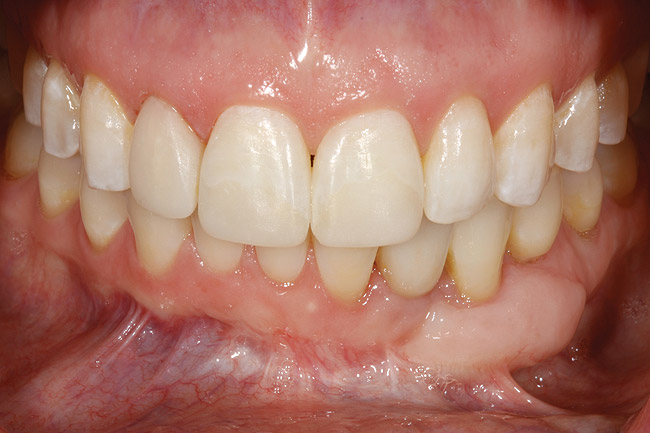

Figure 24  Definitive restoration of tooth No. 23.

Figure 24

Figure 25  Postoperative view of definitive restorations teeth Nos. 7 to 9 and No. 23.

Figure 25

Following the first goal of orthodontia—moving tooth No. 22 to a proper functional and anatomical position—a periodontal reevaluation was performed, demonstrating an improvement in short- and long-term tooth prognosis. At this time, the decision was made to abort continual extrusion of teeth Nos. 21 and 22, although some attachment level discrepancy remained between Nos. 21 and 22 (Figure 14). Implant diagnostics ensued and included mounted study models and a diagnostic wax-up. A scanning appliance was created to demonstrate the desired prosthetic outcome requirements, and the patient was referred for computed tomography (CT) scans. CT scan assessment demonstrated successful orthodontically directed GBR to allow implant placement (Figure 15 through Figure 16). Only minor GBR therapy would be needed and could be accomplished simultaneously with implant installation. Guided implant placement occurred, using an open flap approach (Figure 17). During surgery, root dehiscences were noted on teeth Nos. 21, 22, 24, and 25, as well as the anticipated dehiscence following implant placement at No. 23 (Figure 18). A positioning reference (index) was secured after implant placement to facilitate a provisional prosthesis at stage II surgery. Cortical perforations then were placed adjacent to the implant to encourage angiogenesis (Figure 18), and mineralized freeze-dried bone allograft enhanced with platelet-derived growth factor was placed over the dehiscences for purposes of guided tissue regeneration and GPR (Figure 19). A highly resorbable collagen membrane was placed to stabilize the allograft. The flap was coronally repositioned, and primary-intention wound healing was achieved (Figure 20 and Figure 21). Following 4 months of stage I surgery, implant uncovery and immediate provisionalization was performed in conjunction with connective tissue grafting. Final orthodontic tooth movement then ensued, using the implant as anchorage to optimize end-tooth movements, interroot separation, and the cuspid-protected occlusal scheme. A final impression then was secured, and a zirconia abutment (Figure 22) with an all-ceramic restoration was fabricated for the prosthetic phase completion of No. 23 (Figure 23] through Figure 25).